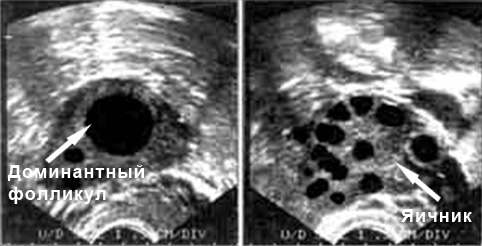

В нормальных условиях у женщин репродуктивного возраста левый и правый яичник имеют схожие размеры. Длина яичников может колебаться от 30 до 41 мм, ширина — от 20 до 31 мм. Толщина этих парных органов составляет от 14 до 22 мм. Объем как правого, так и левого яичника приблизительно равен 12 кубическим миллиметрам. На ультразвуковом исследовании яичники выглядят бугристыми, так как на их поверхности располагаются созревающие фолликулы. В среднем в фолликулярном аппарате насчитывается около 12 зрелых фолликулов, однако в зависимости от индивидуальных особенностей организма их количество может варьироваться. Если в обоих яичниках созревает менее пяти фолликулов, это считается отклонением, требующим коррекции. В начале менструального цикла каждый фолликул имеет диаметр от 3 до 8 мм. При проведении УЗИ в середине цикла врач должен обнаружить доминантный фолликул, размер которого может достигать 24 мм. Вскоре из этого доминантного фолликула выйдет яйцеклетка, а на месте его расположения в период овуляции будет формироваться желтое тело.

Доминантный фолликул на УЗИ

Эффективность функционирования желтого тела можно оценить по его размеру на 18-23 день цикла. Среди патологий, которые могут препятствовать зачатию и нормальному течению беременности, врачи чаще всего упоминают кисты яичников и отсутствие доминантного фолликула, что указывает на отсутствие овуляции. Вопрос о том, какая терапия для лечения кисты яичника будет наиболее подходящей в каждом конкретном случае, решает лечащий гинеколог. Отсутствие доминантного фолликула или его неправильное функционирование может быть связано с развитием раннего климакса или дисфункцией яичников. Оба этих состояния сегодня успешно корректируются с помощью курса гормональных препаратов.